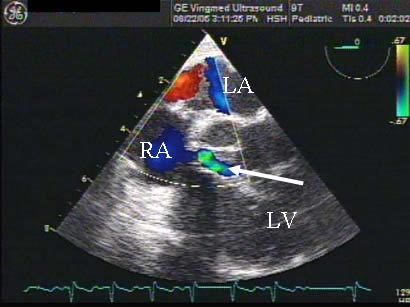

A seven-year-old girl presented to the emergency room (ER) with a six-day history of nausea, vomiting, and fevers. She has a history of aortic coarctation repair at 6 months of age. Symptomatically, she did well after that surgery, but had been followed for a residual coarctation. She presented to the ER hypotensive and was given three boluses of fluid and subsequently started on dopamine and transferred to the Pediatric Intensive Care Unit. Her C-reactive protein (CRP) and erythrocyte sedimentation rate (ESR) were elevated. Her physical exam revealed a V/VI holosystolic ejection murmur heard over the entire sternal border and diffuse crackles. An electrocardiogram revealed sinus tachycardia without heart block. Her blood culture on admission grew methacillin sensitive Staphylococcus aureus. She was started on Vancomycin and Cefotaxime. Cardiology was consulted secondary to her history of congenital heart disease and the possibility of endocarditis. An echocardiogram revealed a large mass in the RA located superior to the tricuspid valve septal leaflet and moderate to severe tricuspid valve regurgitation (TR). There was question of a left to right shunt from either the LV or aorta to the RA. A computed tomographic (CT) angiogram of the chest demonstrated there was a connection between the LV and RA, minimal residual coarctation, and an embolus occluding the left pulmonary artery (PA) (Figures 1, 2a, and 2b). She had persistent bacteremia and septicemia despite antibiotics, with progressive pulmonary edema. Less than 24 hours after cardiology was consulted, the patient was emergently taken to the operating room with the diagnosis of an acquired Gerbode defect and pulmonary embolism.

Preoperative transesophageal echocardiography (TEE) reconfirmed the preoperative diagnosis of a large LV-to-RA shunt, a large RA mass, and moderate to severe TR (Figures 3 and Video 1). Using cardiopulmonary bypass, she was cooled down to 24°C and cardiac arrest was achieved with antegrade cardioplegia. Externally, we could see that the left PA before the first branch was filled with a mass and was discolored. Through a right atriotomy, a large 2 cm x 1.5 cm vegetation in the RA, which served as a windsock-type tunnel for the LV-to-RA shunt, was identified (Figure 4a). This windsock connection was located right above the tricuspid valve and encroached on the base of the commissure between the septal and anterior leaflets, directly in the area of the conduction system. There were drop vegetations on the tricuspid valve besides the encroaching mass, all of which were causing tricuspid regurgitation. The aorta was then opened and the aortic valve was examined. The defect in the LV was in the intra-trigonal area between the right coronary and noncoronary cusps of the aortic valve (Figure 4b). There were also several drop vegetations on the aortic valve as well as on the mitral valve chordae. These vegetations were resected. The windsock-type mass in the right atrium was resected revealing a one centimeter defect from the RA into the LV just above the tricuspid valve annulus. This defect represented a type of acquired Gerbode defect. We were quite surprised that the conduction system was not compromised preoperatively since the defect eroded into the apex of the triangle of Koch.

Preoperative diagnosis of an LV-RA communication is often very difficult. TEE has been demonstrated to be superior to trans-thoracic echocardiography (TTE) in identifying not only vegetations and valvar pathology, but also associated complications of endocarditis such as abscess and fistula formation [5]. In our patient, the preoperative diagnosis of a vegetation and an LV-to-RA communication was suspected by TTE, however the vegetation in the right atrium was not the typical oscillating type but rather a fixed mass just above the TV. This appearance can be typical for an aortic or ventricular to atrial shunt as echogenic debris builds up in this area of turbulent flow creating a windsock, as seen here (Figure 4a). Since the diagnosis remained unclear, a CT was performed primarily to assess the prior coarctation repair, but also we hoped it would better define the possible intracardiac shunt. The CT clearly identified the LV-to-RA shunt but also revealed a large pulmonary artery embolus (Figures 1-2). CT scan and MRI are diagnostic options in addition to echocardiogram in this disease process, especially as the speed at which one can obtain and perform a cardiac MRI continues to improve.